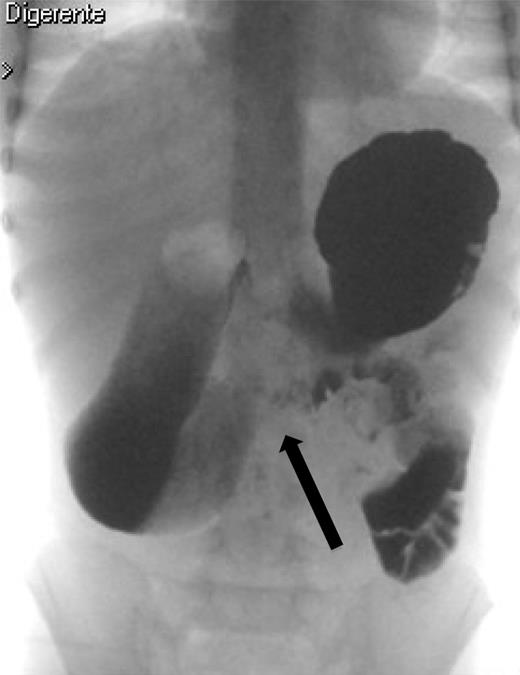

A 7-year-old boy who had been treated at 3 years of age for a subtotal colonic Hirschsprung disease with a Deloyers’ procedure was admitted for persistent bilious vomit associated with recurrent episodes of postprandial abdominal pain and diarrhea. The parents reported a progressive weight loss of 3.5 kg during the last 3 years. The patient was emaciated with severe chronic malnutrition; the weight and the length were 15.19 kg and 113 cm [body mass index (BMI): 11.9 kg/m2], both between the third and the fifth percentile, respectively. The clinical abdominal examination was normal. A plain abdominal X-ray showed a distended stomach with paucity of gas in the distal bowel. An abdominal ultrasound confirmed a dilated duodenum without signs of mechanical obstruction of the small bowel and a normal relationship between the superior mesenteric vessels. An upper gastrointestinal contrast study confirmed dilatation of the first and second portions of the duodenum with little progression of contrast medium across the third portion released in left lateral position (Fig. 1). An SMAS was confirmed by a computed tomography (CT) scan that showed a reduction in retroperitoneal preduodenal and mesenteric fat and compression of the third duodenum by the superior mesenteric artery with an acute 13° angle and a 7.5 mm distance from the aorta (Fig. 2). A gastrointestinal endoscopy confirmed the dilatation of the duodenum with an inflammatory mucosa and a normal jejunum. Gastric and duodenal biopsies were performed and a nasojejunal tube was guided through the duodenum to the Treitz to start enteral feeding (Fig. 3).

The upper gastrointestinal contrast study shows poor progression of contrast medium across duodenal obstruction. Arrow shows obstruction of the third duodenum.